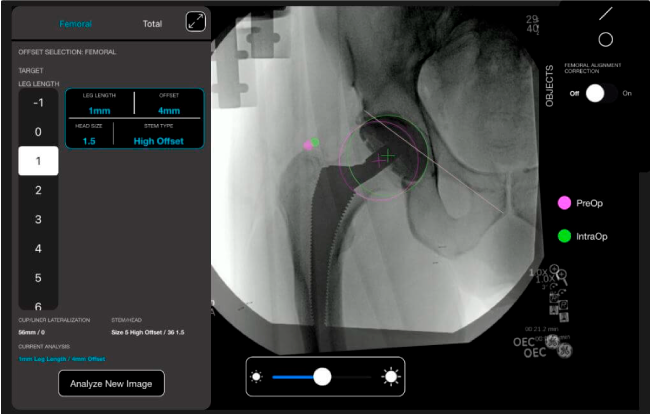

Planeación preoperatoria mediante la creación de plantillas digitales para reemplazo de cadera y análisis intraoperatorio

Datos procesables en tiempo real para la toma de decisiones.

Mayor nivel de información intraoperatoria facilita la colocación correcta de los implantes:

Desplazamiento y offset para posicionamiento óptimo del componente (vástago) femoral.

Anotaciones digitales y herramientas de análisis de longitud de pierna.

Con tecnología ONETRIAL® que calcula automáticamente el cambio en la longitud de la pierna y el desplazamiento para todas las combinaciones de implantes en una tabla fácil de leer.